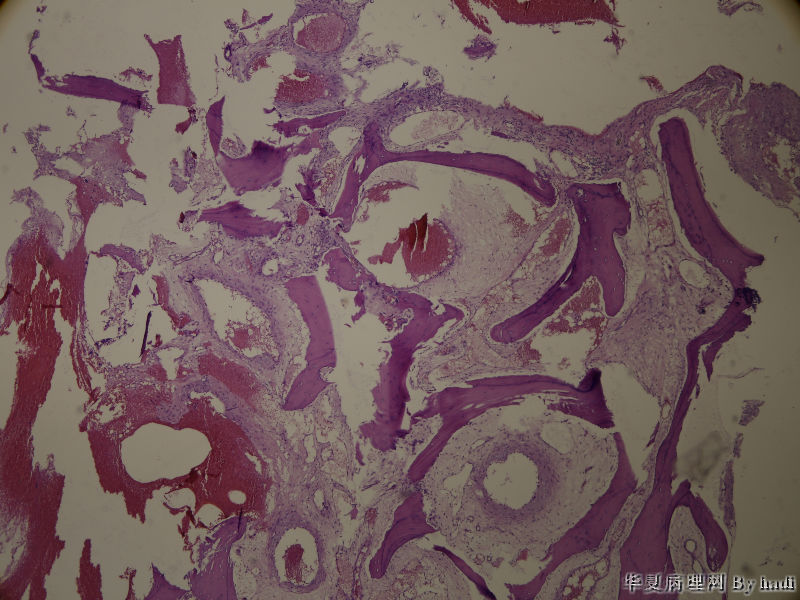

鼻腔肿瘤

鼻腔肿瘤,成人男性

纤维血管瘤?看不清间质有无异型

血管瘤

血管瘤。

排除一下神经鞘瘤

神经鞘瘤